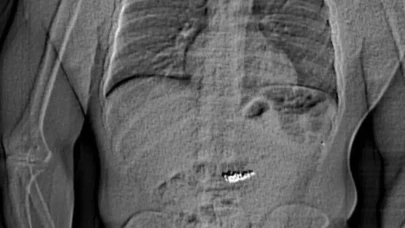

Florida’da lüks mücevher mağazasından çalınan 769 bin dolar değerindeki küpeleri yutan şüpheli gözaltına alındı